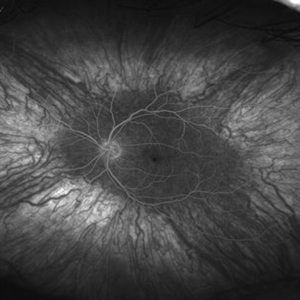

Anterior Ischemic Optic Neuropathy and Choroidal Ischemia

Mar 1 2014 by Homayoun Tabandeh, MD, FASRS

Fundus fluorescein angiogram of a patient with arteritic anterior ischemic optic neuropathy and choroidal ischemia associated with giant cell arteritis.

Condition/keywords: anterior ischemic optic neuropathy